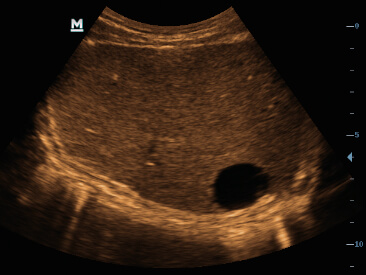

Clinical Images

-Hepatic cyst

-Hepatic hemangioma